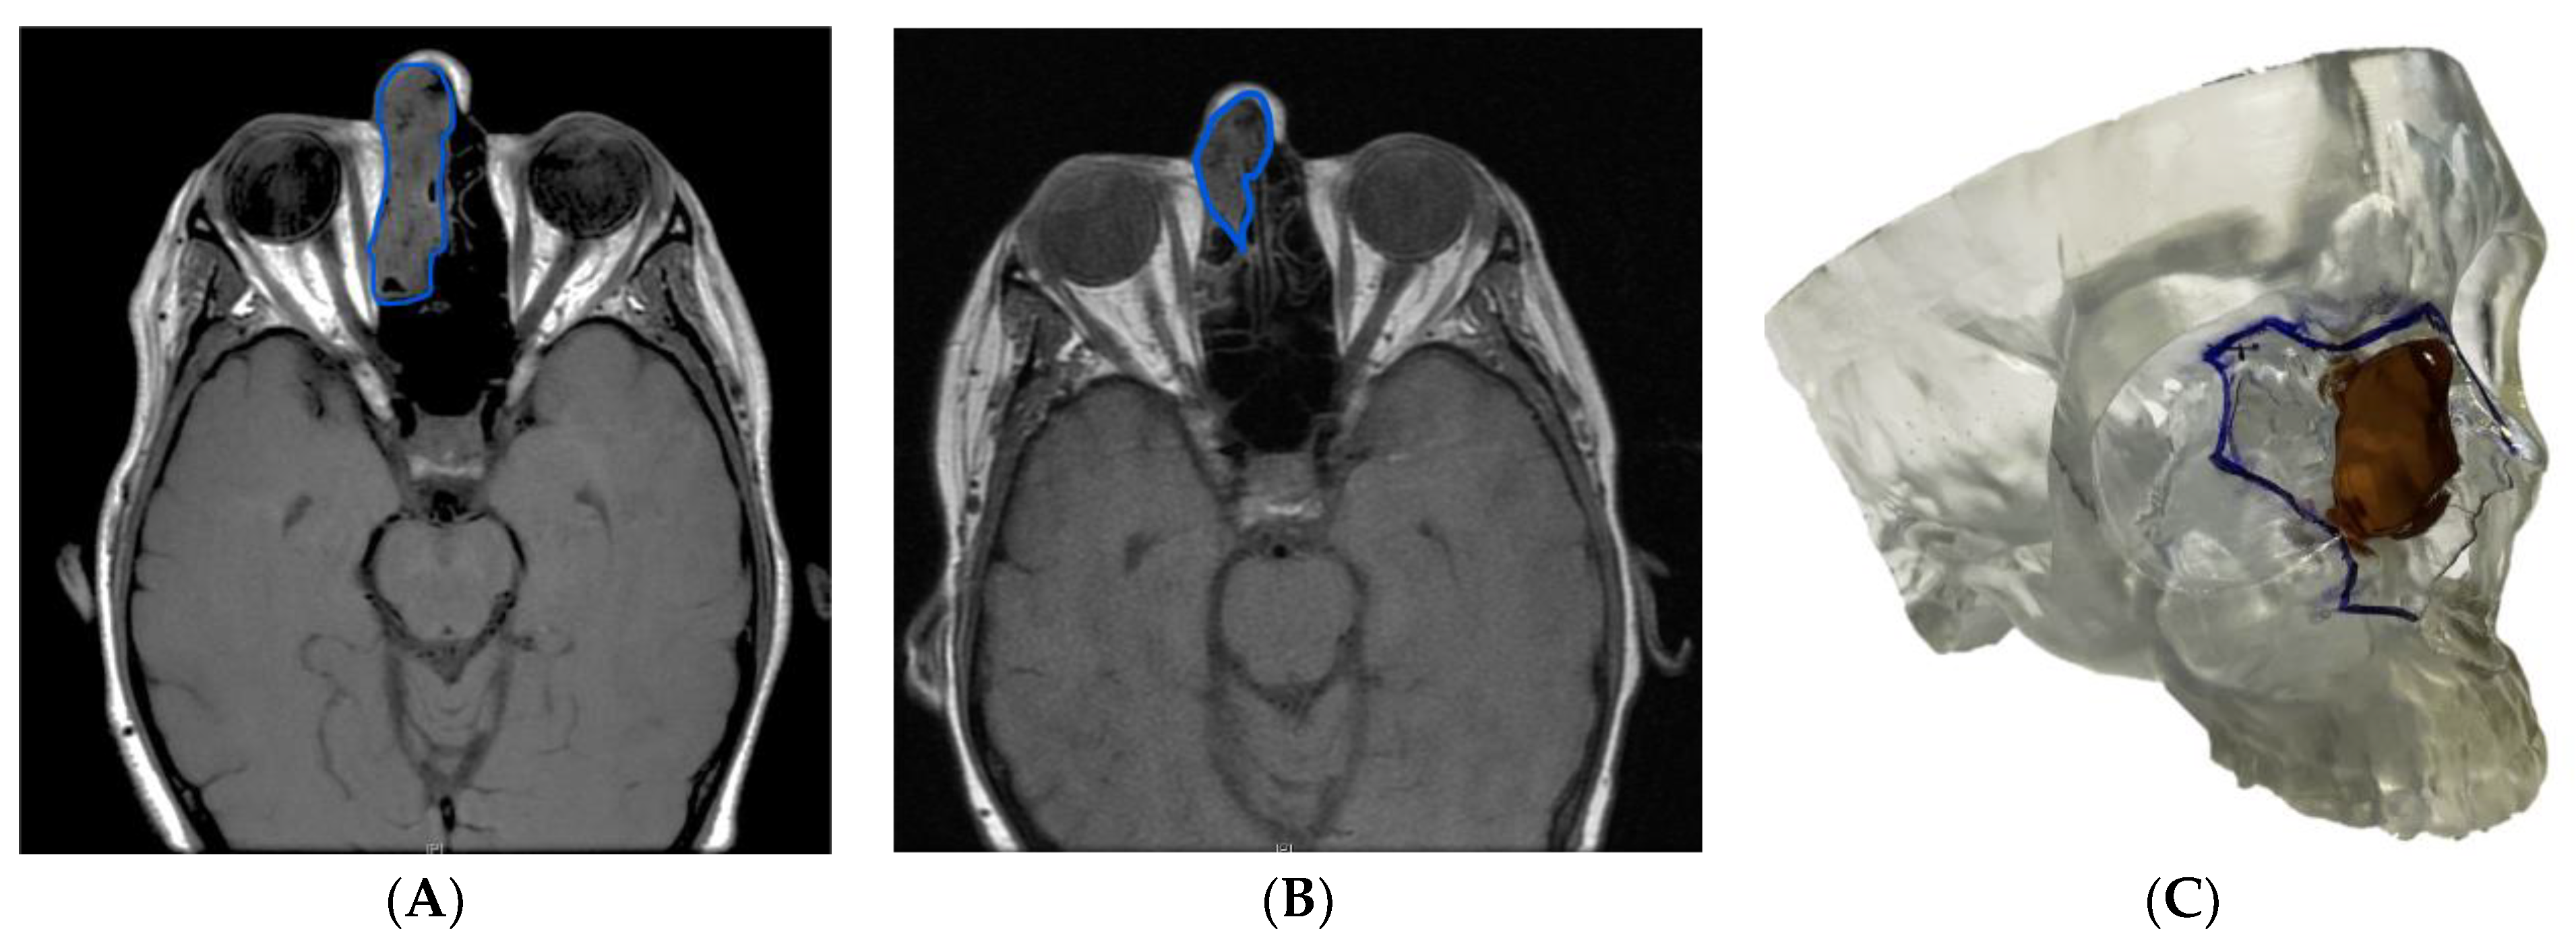

3.1.5. Case 5: The Role of Virtual Surgical Planning and a 3D Model in Multidisciplinary Teamwork